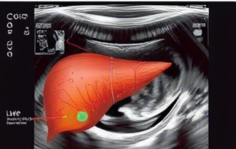

복부 초음파란?

복부 초음파는 간, 담낭, 췌장, 신장, 비장 등 복부 내 주요 장기의 상태를 확인하는 비침습적 진단 검사입니다.

통증, 간질환, 담석, 췌장염 등 다양한 질환의 초기 발견에 중요한 역할을 하며, 건강검진이나 특정 증상으로 인한 진료 시 흔히 시행됩니다.